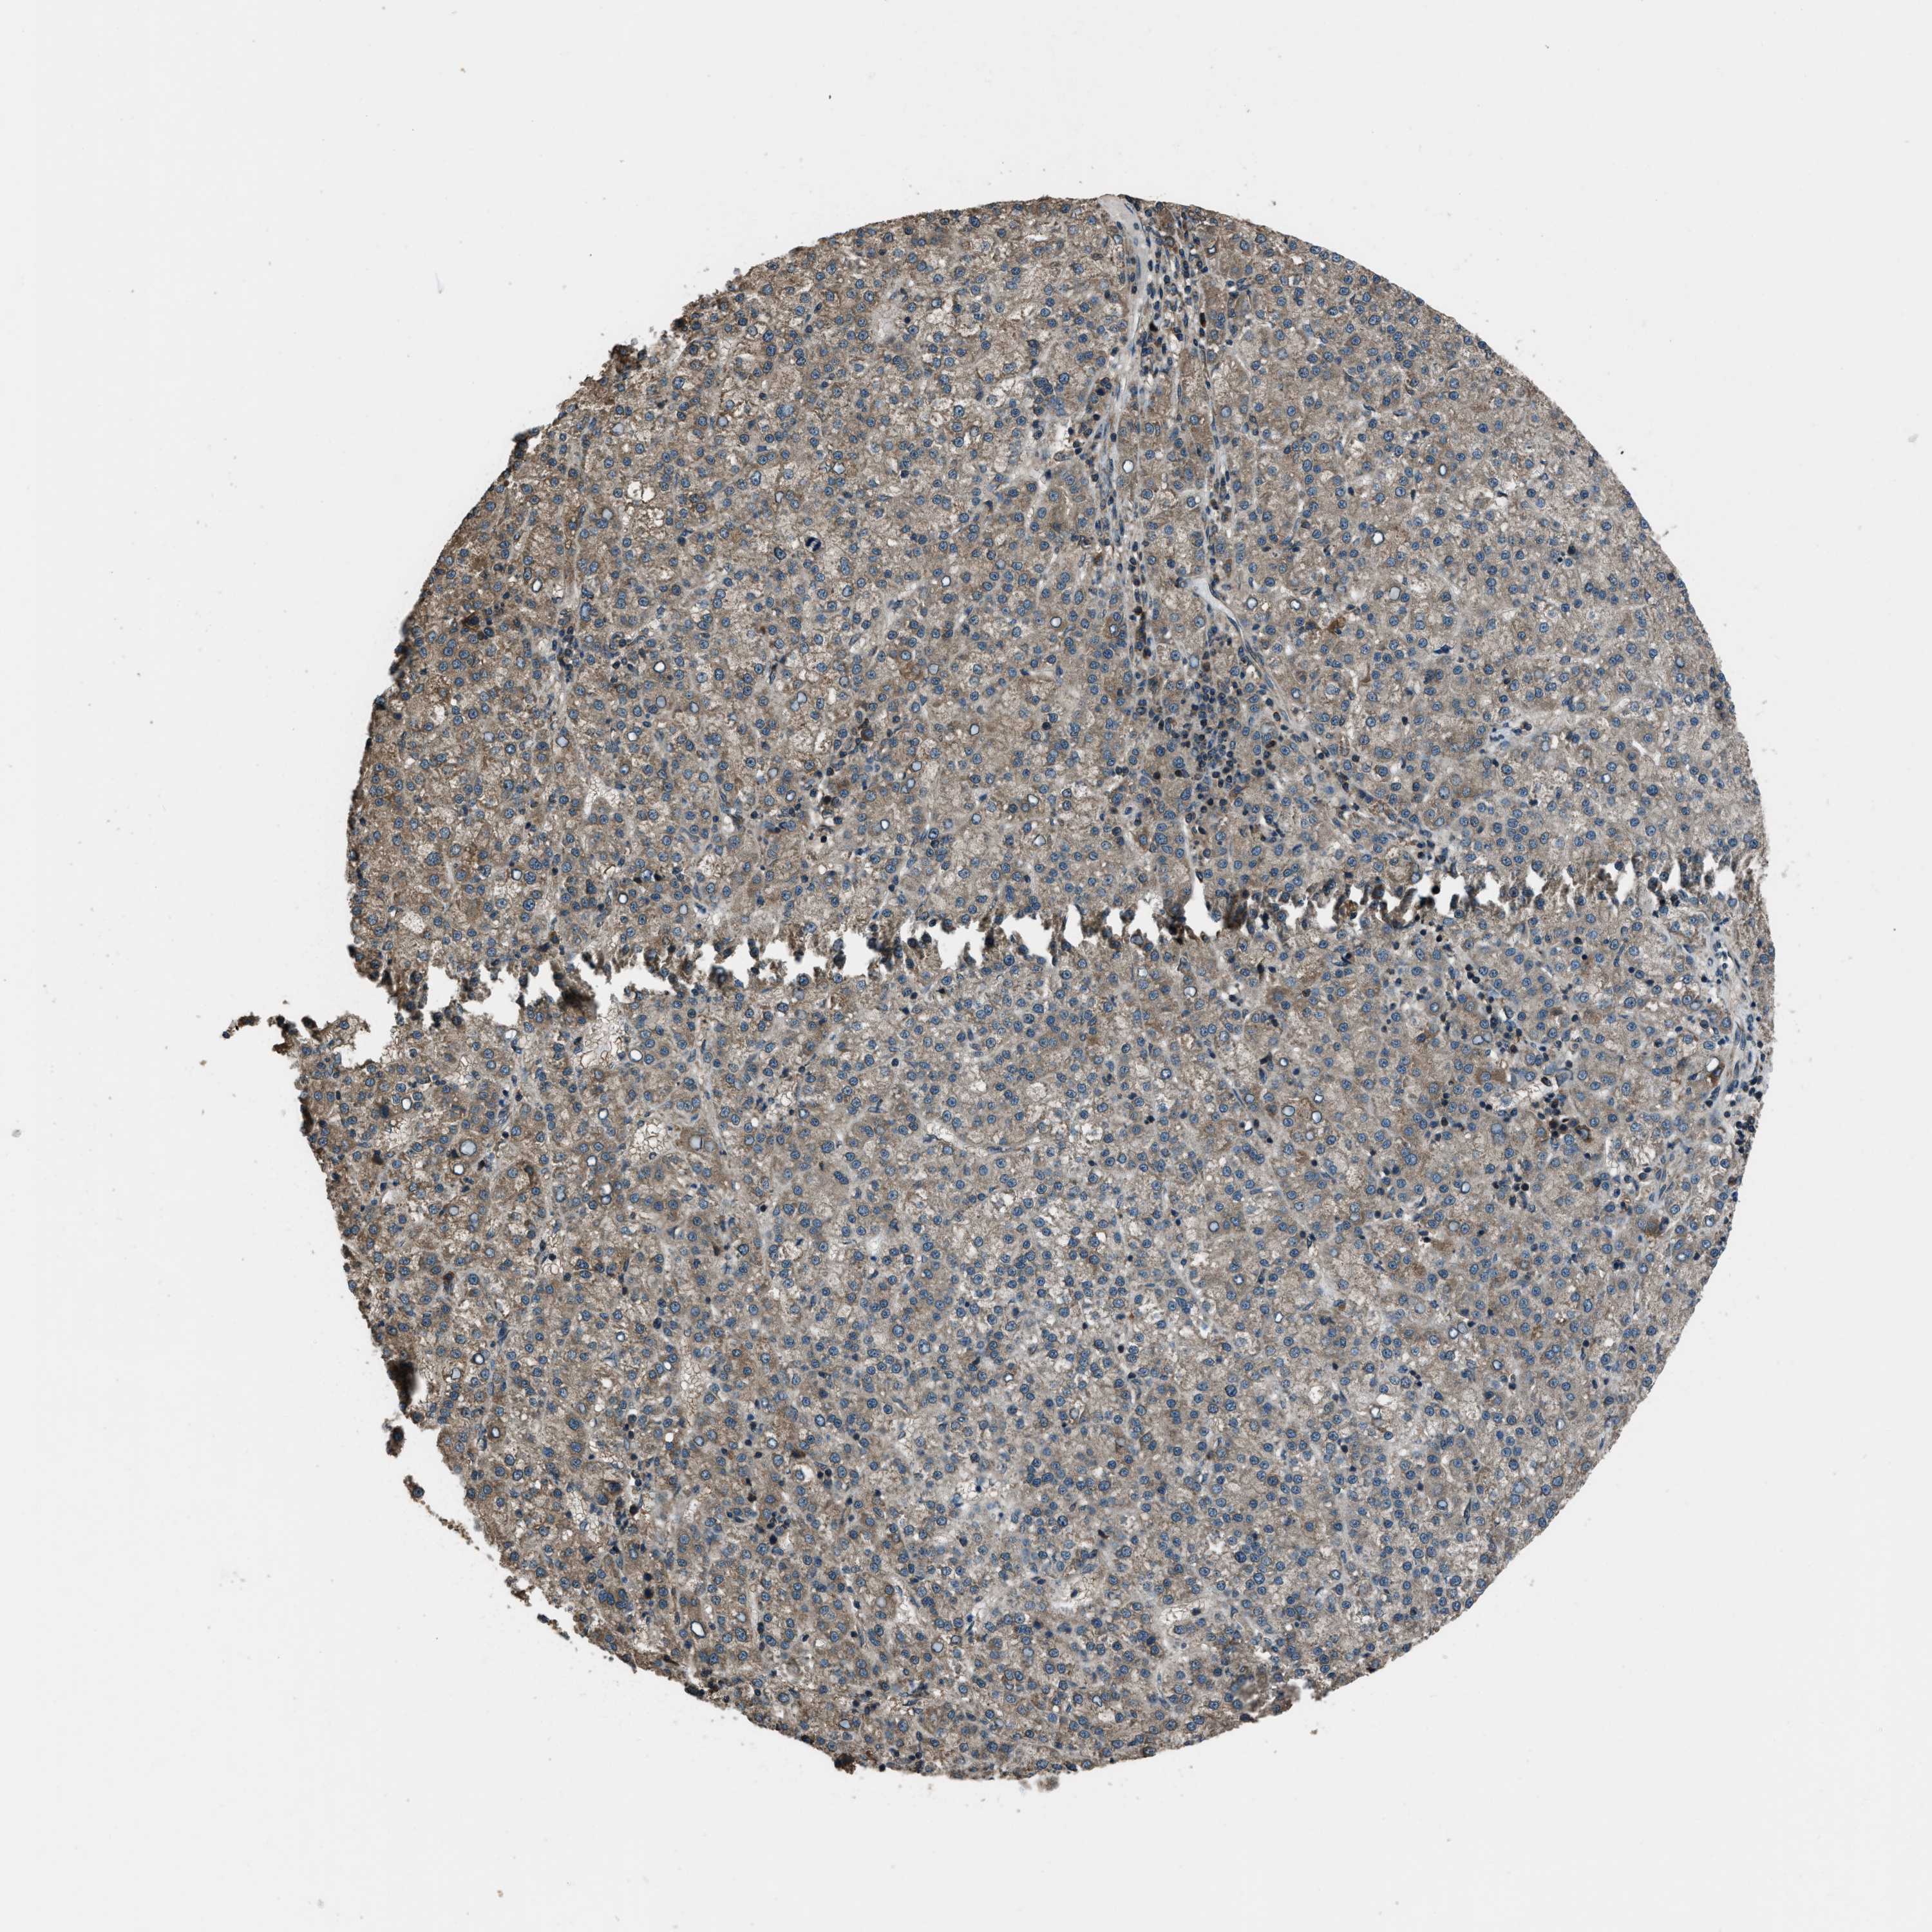

LIVER CANCER - Protein expressioni

A mouse-over function shows sample information and annotation data. Click on an image to view it in a full screen mode. Samples can be filtered based on level of antibody staining by selecting one or several of the following categories: high, medium, low and not detected. The assay and annotation is described here.

Note that samples used for immunohistochemistry by the Human Protein Atlas do not correspond to samples in the TCGA dataset.

Antibody stainingi

Antibody staining in the annotated cell types in the current human tissue is reported as not detected, low, medium, or high, based on conventional immunohistochemistry profiling in selected tissues. This score is based on the combination of the staining intensity and fraction of stained cells.

Each image is clickable and will lead to virtual microscopy that enables deeper exploration of all samples and also displays staining intensity scores, fraction scores and subcellular localization as well as patient and tissue information for each sample.

Antibody HPA019356

Antibody HPA029461

Staining

High

Medium

Low

Not detected

Intensity

Strong

Moderate

Weak

Negative

Quantity

>75%

75%-25%

<25%

None

Location

Nuclear

Cytoplasmic/membranous

Cytoplasmic/membranous,nuclear

Cholangiocarcinoma

Carcinoma, Hepatocellular, NOS